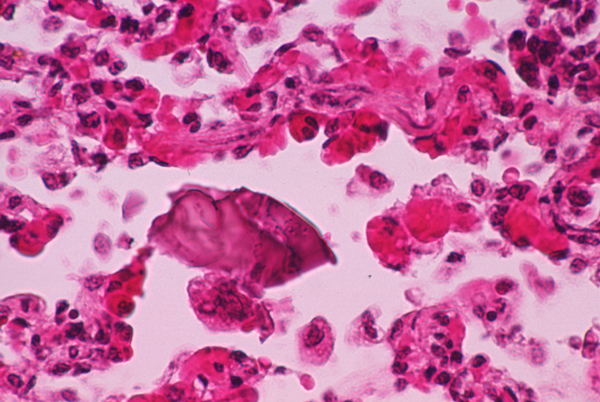

002